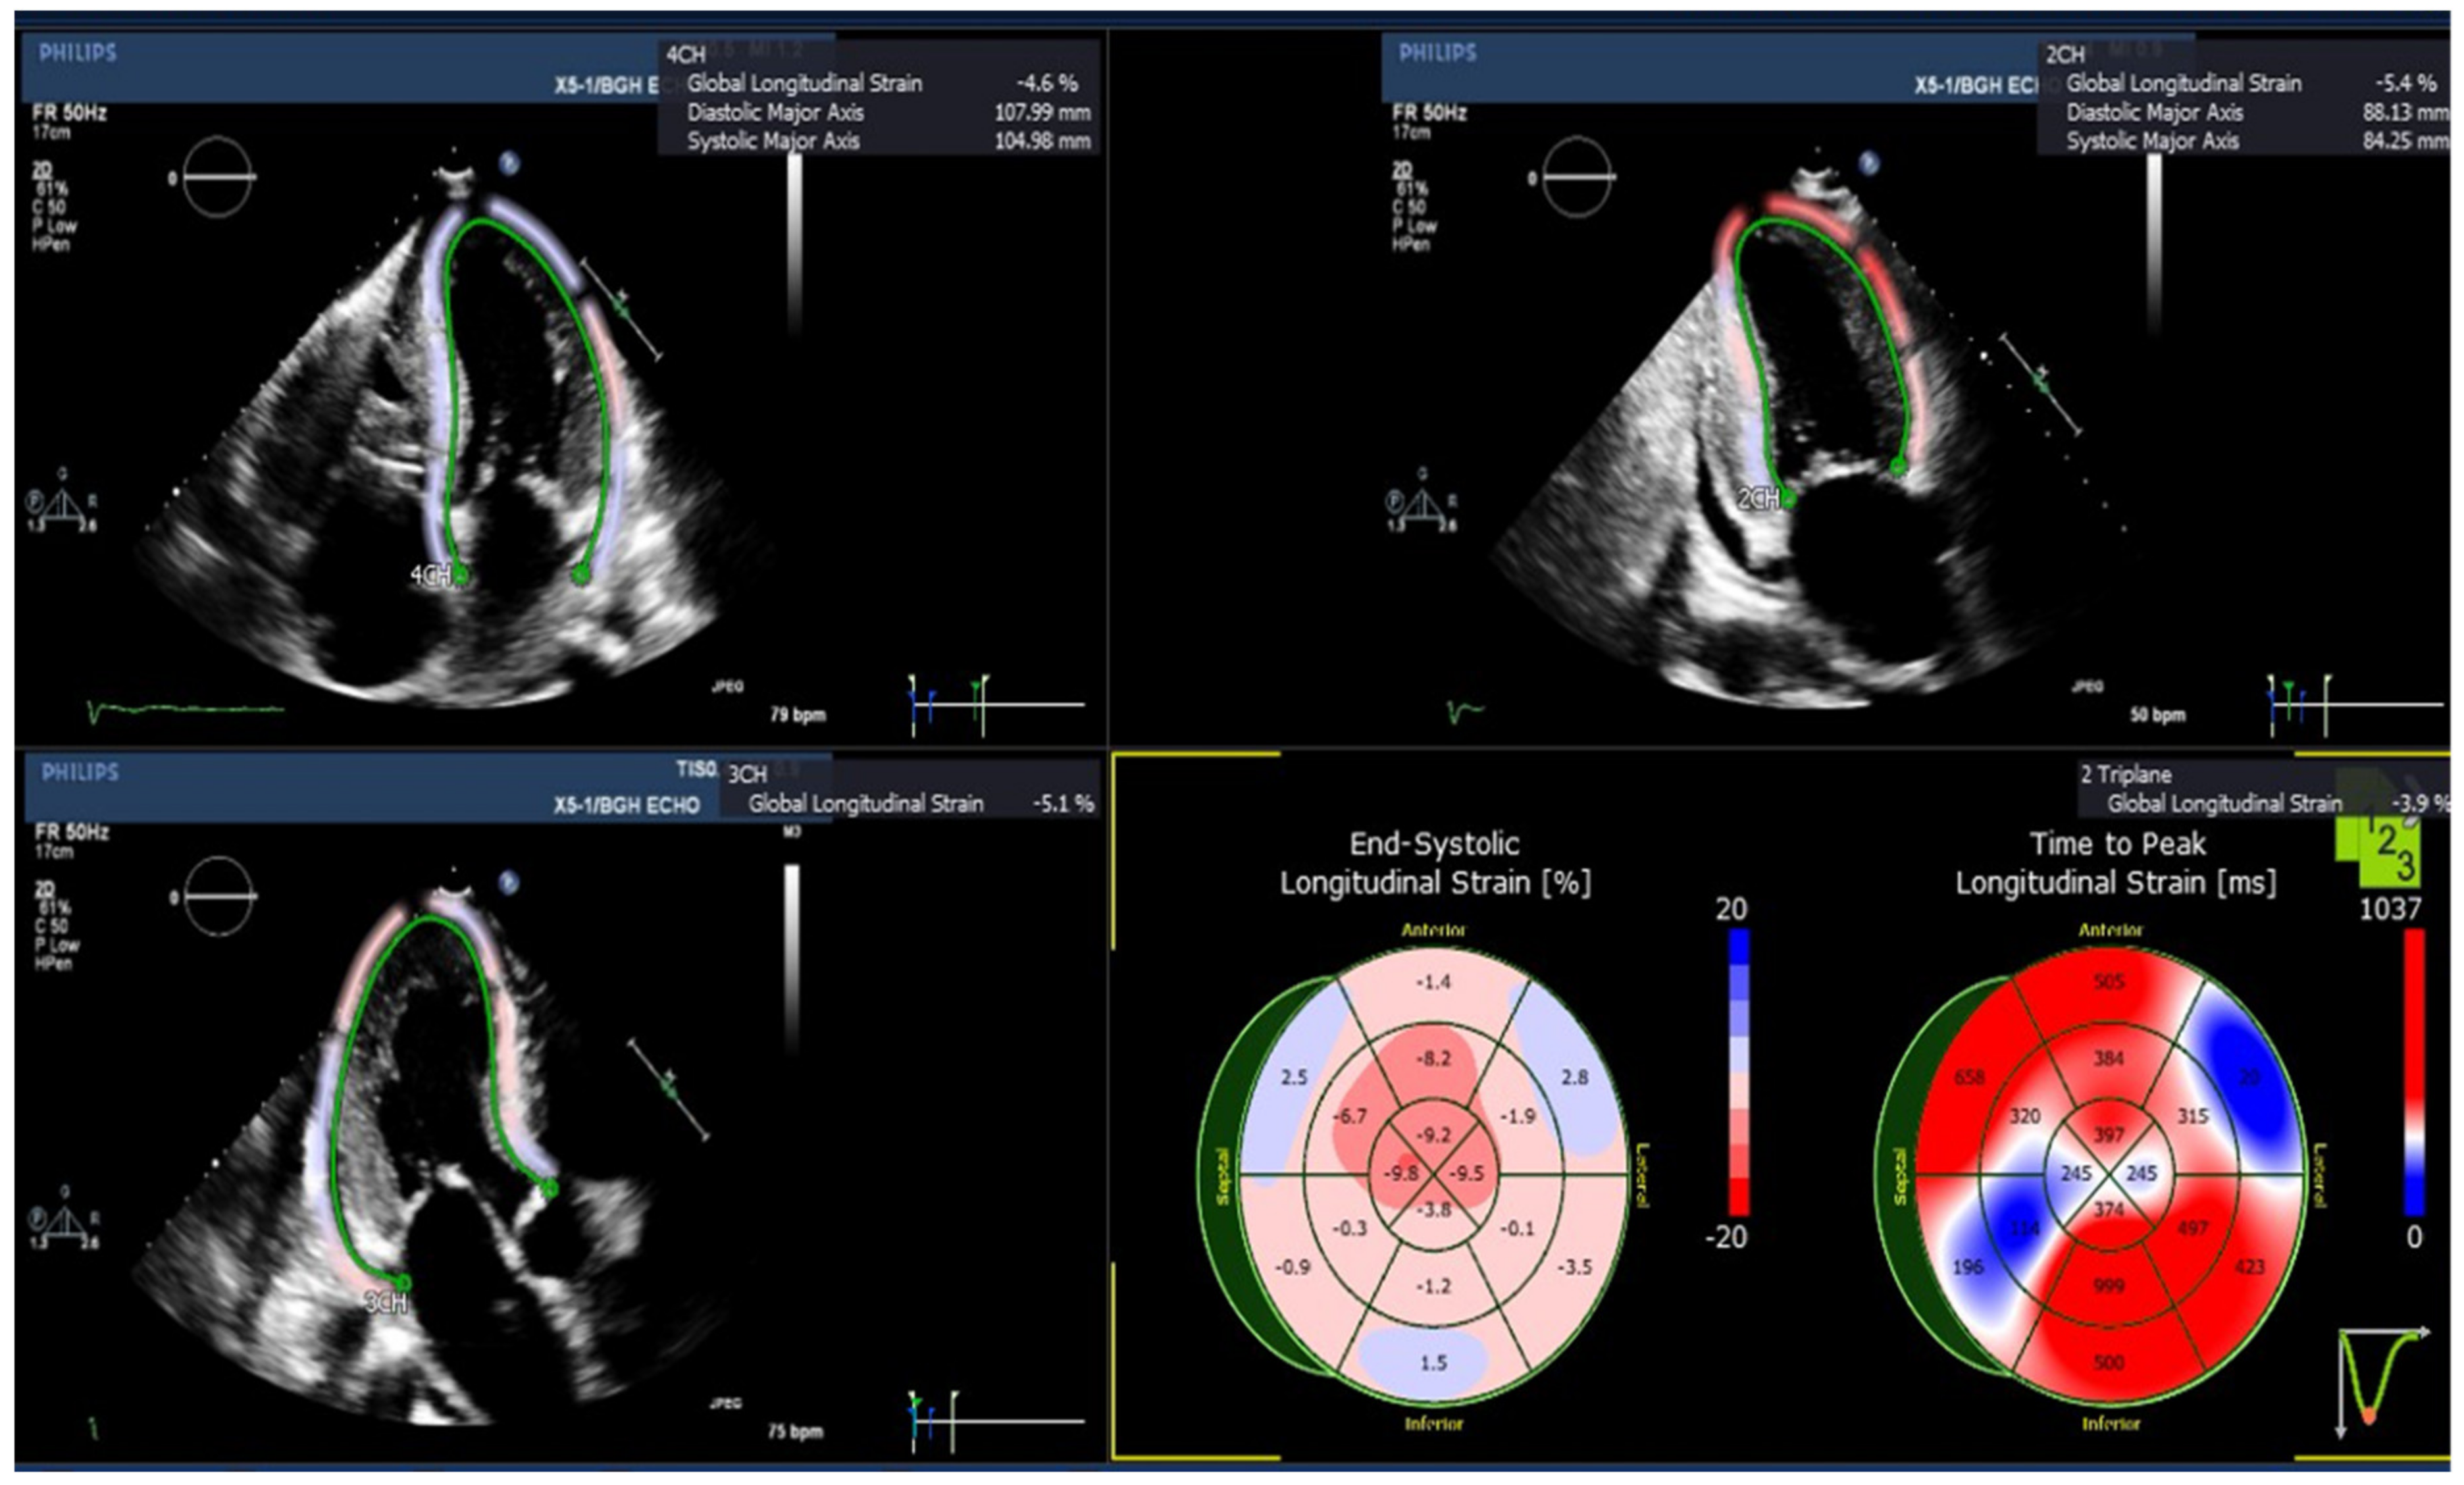

3.2. Echocardiographic Assessment of Left Ventricular (LV) Longitudinal Strains

| GLS (%), Mean (SEM) | Amyloid Patients (n = 5) | Normal Subjects (n = 8) |

| GLS, triplane | −7.96 (1.45) * | −19.44 (0.33) |

| GLS, apical four chamber | −9.10 (1.42) * | −21.51 (0.62) |

| GLS, apical two chamber | −8.12 (1.72) * | −19.35 (0.77) |

| GLS, apical three chamber | −8.0 (1.11) * | −18.45 (0.64) |

| Basal anterior | −4.54 (1.60) * | −26.65 (1.57) |

| Basal anteroseptal | −2.42 (2.10) * | −15.78 (3.38) |

| Basal inferoseptal | −5.96 (1.66) | −16.85 (4.61) |

| Basal inferior | −3.44 (2.17) * | −20.26 (3.65) |

| Basal inferolateral | −8.5 (2.92) * | −32.54 (3.13) |

| Basal anterolateral | −5.88 (3.09) * | −34.56 (2.77) |

| Mid anterior | −6.62 (1.10) * | −15.23 (1.80) |

| Mid anteroseptal | −6.88 (1.94) * | −16.83 (2.50) |

| Mid inferoseptal | −5.74 (1.97) * | −18.15 (2.34) |

| Mid inferior | −6.40 (1.5) * | −16.15 (2.20) |

| Mid inferolateral | −1.96 (1.91) * | −10.74 (1.97) |

| Mid anterolateral | −3.30 (1.33) * | −16.23 (2.11) |

| Apical anterior | −12.94 (4.27) | −15.95 (2.49) |

| Apical septal | −14.50 (2.83) * | −20.86 (1.29) |

| Apical inferior | −11.76 (3.60) | −19.20 (1.70) |

| Apical lateral | −13.32 (1.55) | −17.23 (2.66) |